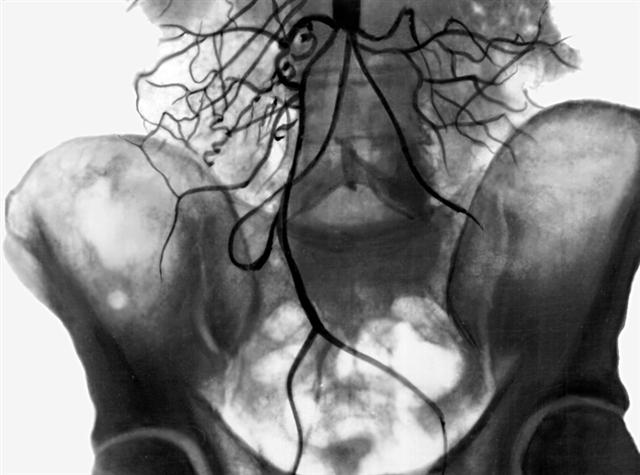

Аортограмма при высокой окклюзии брюшной части аорты

Рис. 3. Аортограмма при высокой окклюзии брюшной части аорты: видны многочисленные коллатерали, берущие начало выше уровня окклюзии аорты.